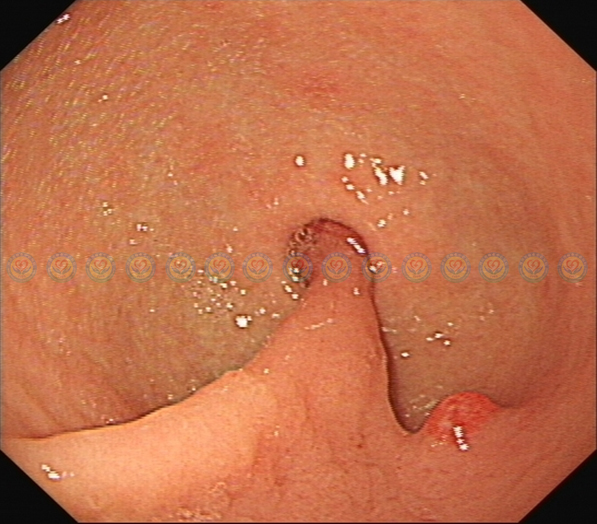

进镜至胃窦,幽门处见肿块嵌顿。

近观,有肿块嵌顿于幽门口,表面糜烂渗血,有粗蒂与胃窦大弯侧相连。